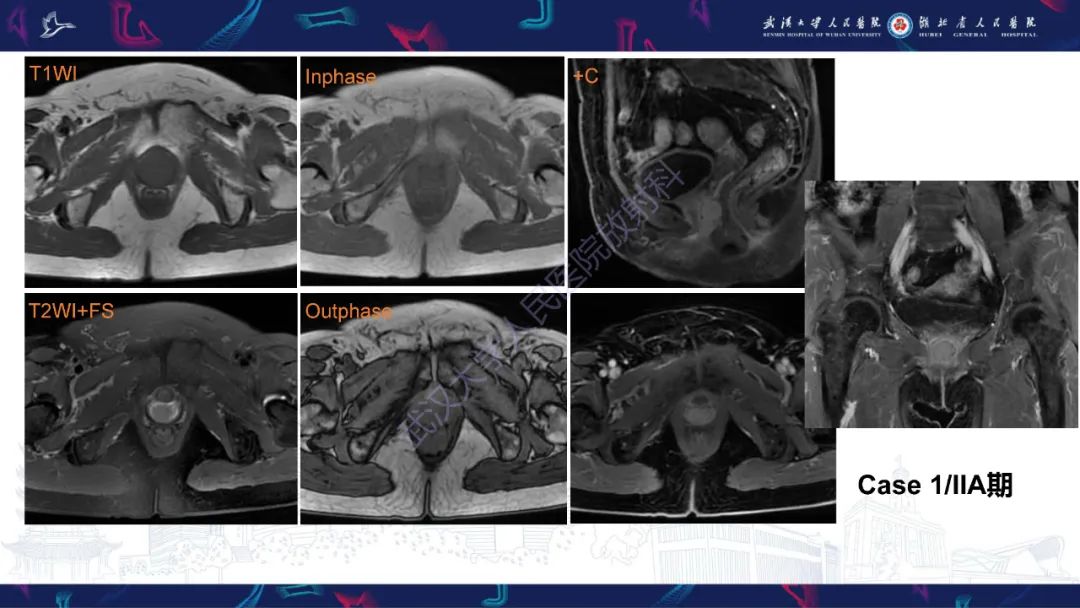

【PPT】阴道髓系肉瘤影像诊断-1